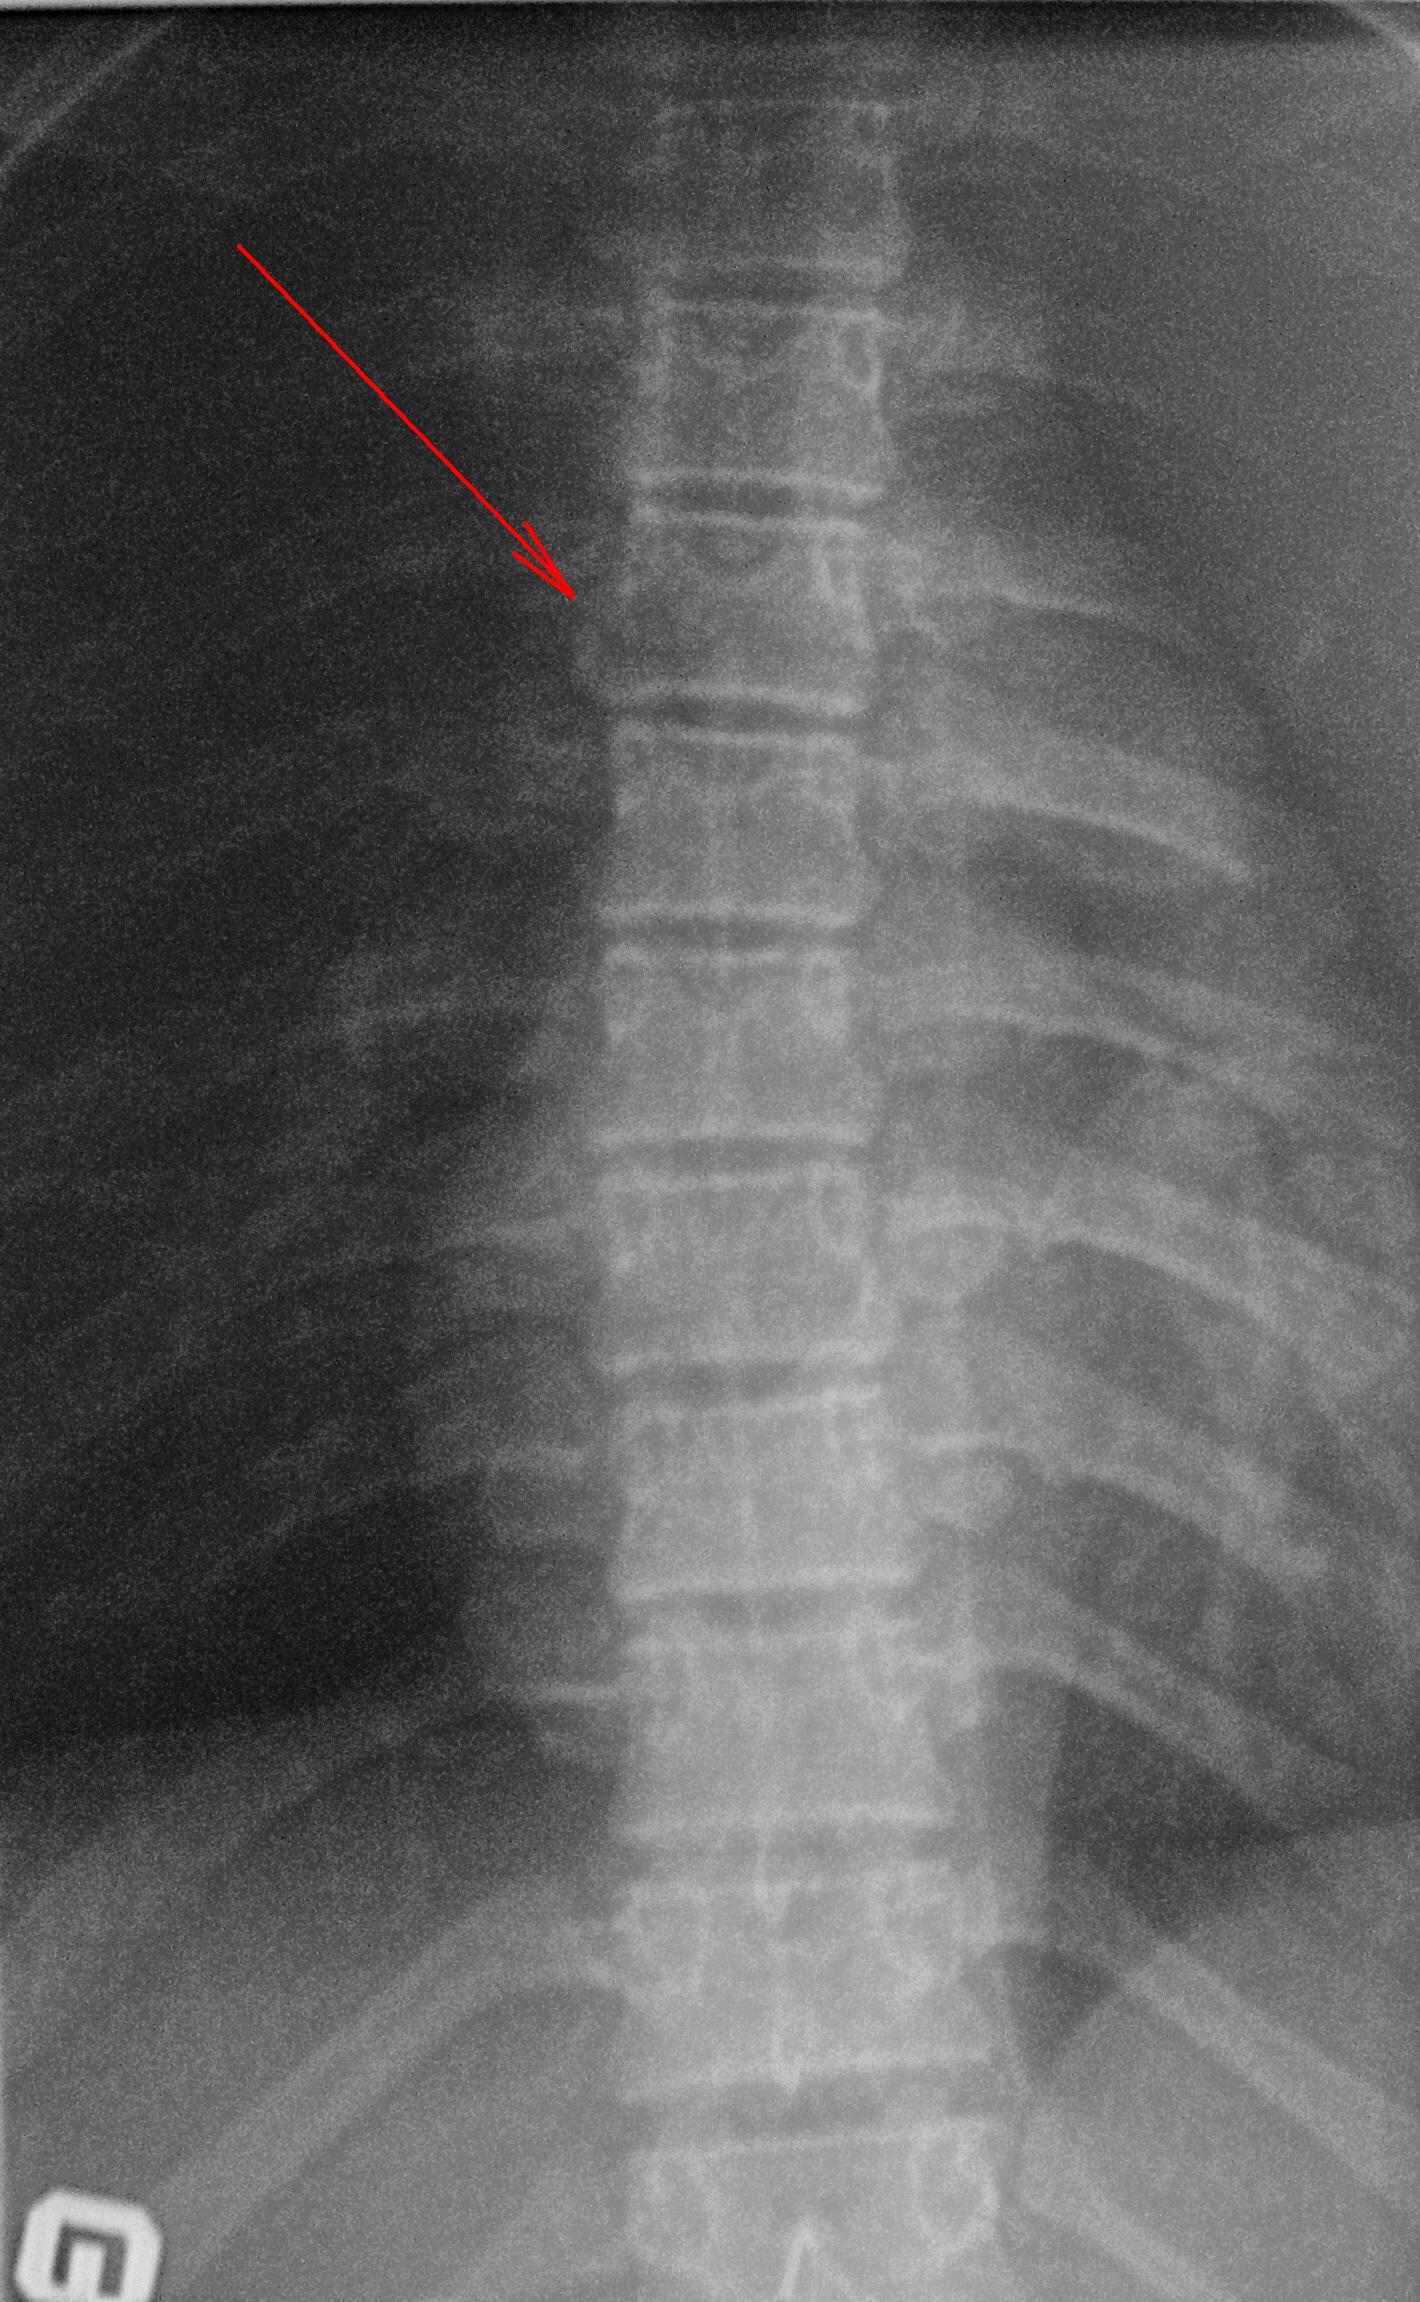

Рентгеновские снимки и медицинские изображения компрессионных переломов